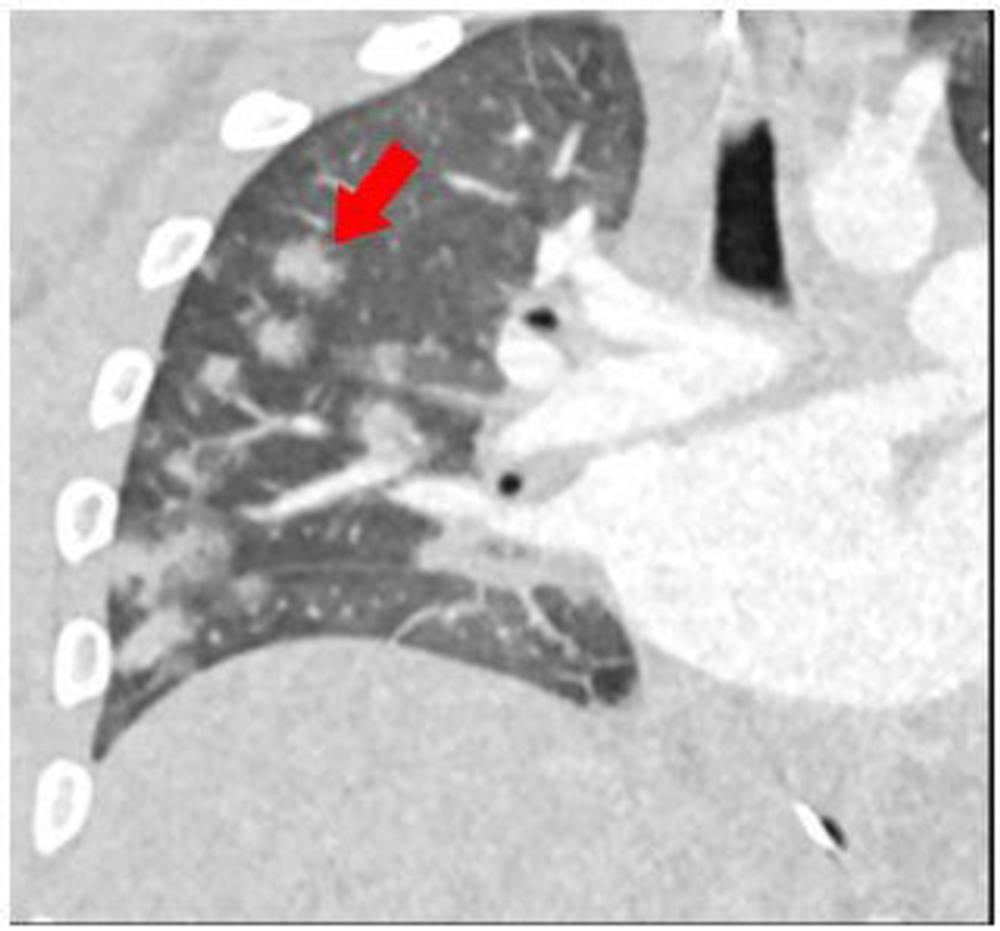

Figure 4. 15-year-old male presenting with fever, sepsis, and shock with impaired cardiac function. Coronal reconstruction of a contrast-enhanced CT chest shows multiple round consolidative foci with surrounding ground glass halos (red arrow).

High-res (TIF) version